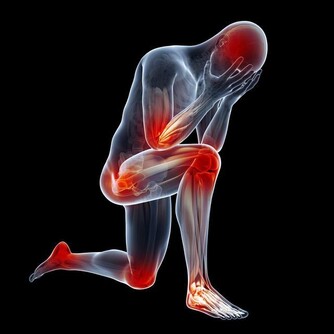

3. 肌肉無力

腫瘤如果影響到大腦或腦幹中的脆弱組織,可以導致人們喪失力量甚至癱瘓。

何時該擔心:如果你的胳膊、腿部或面部感到軟弱無力或者麻木,並且幾分鐘後還不會消失,

那麼請立即前往急診室。